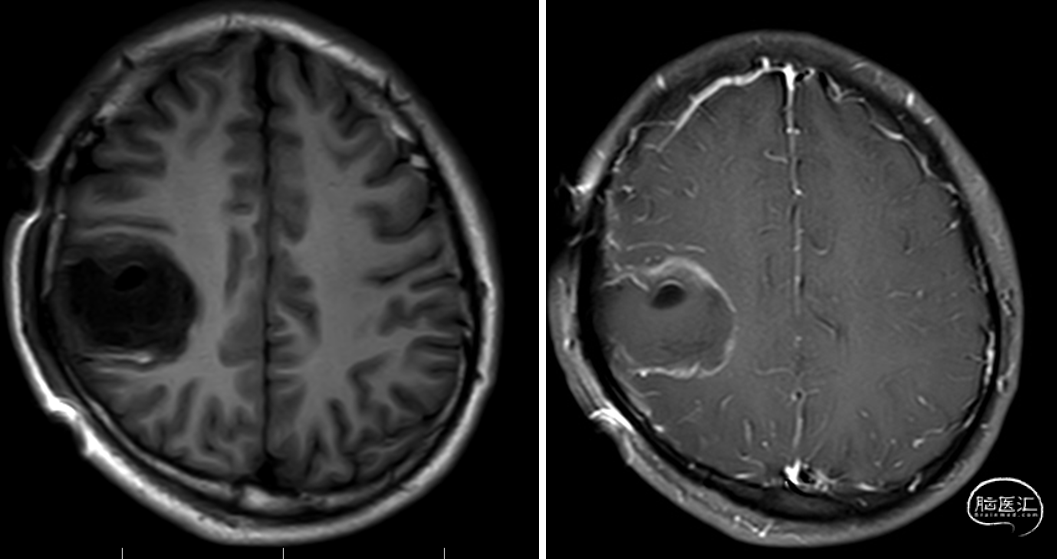

术前影像学检查:

影像学描述:头颅CT提示右侧顶叶低密度病灶;头颅MR提示右侧顶叶见一异常信号肿块,边界尚清,范围约38mm×40mm。病灶T1WI呈稍低信号,T2WI呈稍高信号,增强扫描显示肿块未见明显强化,病灶周围水肿不明显,局部脑沟稍变浅,颅内中线结构向左侧轻微移位。脑池、脑裂未见增宽。颅骨未见异常。

影像诊断:右侧顶叶异常信号肿块,考虑低级别胶质瘤(多为低级别星形细胞瘤可能)。